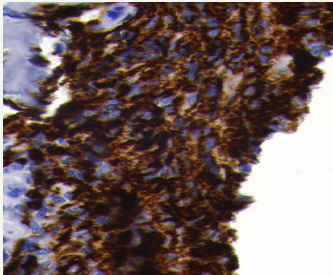

Figure 8: Tumour cells having round, irregular cleaved nuclei with prominent nucleoli and moderate amount of cell cytoplasm with frequent mitotic figures suggestive of round cell tumour.

A 58 year old female presented with pain in the left thigh and pelvis. She was originally radiographed (Figure 1 & 2) and was managed conservatively in the periphery. The radiographed of the skull showed no involvement of skull bones (Figure 3).Then the MRI of the femur and pelvis was done which reported it is as a cystic lesion and was advised extended curettage (Figure 4 & 5). No treatment was done. Two months after this the patient presented to us with greater pain and a pathological fracture left trochanteric region. The patient also had palpable subcutaneous masses in the head. We reviewed the MRI and did CECT pelvis and CECT head. CECT pelvis showed lytic expansile destruction of both the sacral ala with soft tissue masses extending into spinal canal causing compression of the cal sac in addition to the original lesion in the neck and trochanteric region with fracture (Figure 6). CECT head showed multiple lytic areas with formation of soft tissue masses in extra-calvirial and intra cranial locations (Figure 7). The brain parenchyma was normal. We did biopsy of the trochanteric region and nodule from scalp. Both the reports showed large tumour cells having round, irregular cleaved nuclei with 1-2 prominent nucleoli and moderate amount of cell cytoplasm with frequent mitotic figures (Figure 8). On immunohistochemistry were positive for LCA and CD-20 suggesting diffuse large B- cell lymphoma (Figure 9). The patient was then started on CHOP regime.

Figure 9: Immunochemistry– positive for LCA and CD-20 confirming diffuse large b-cell lymphoma.